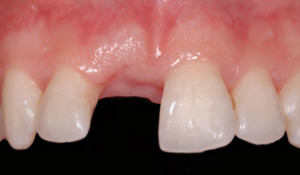

Ma ad un certo punto successe l’imprevedibile.. durante l’ennesima piroetta Impiantolo scivolo’ giù dal palco infilandosi dritto dritto nella mandibola di uno spettatore rimasto a bocca aperta affascinato dalle sue acrobazie…

Improvvisamente spari’… la piazza si ammutolì… lo spettacolo si interruppe..

Gli otto nani rimasero in sette, mentre Impiantolo capi’ che si era avvitato troppo e non riusciva piu’ a uscire dalla bocca del malcapitato.

Impiantolo, dapprima triste e solo, fu invece pian piano avvicinato e abbracciato da tanti nuovi amici: globulino rosso, globulino bianco, piastrina, connettivina, collagenina e tanti altri che lo circondarono di tanto affetto e lo considerarono uno di loro, così che lui si poté sentire finalmente perfettamente integrato!!! …aveva finalmente compreso il suo vero talento.